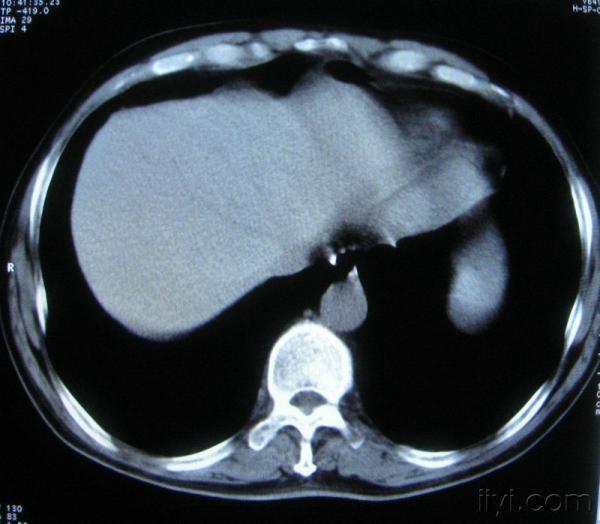

男。60岁,胸片示支气管炎治疗后复查CT。

你指那个肯定是淋巴结,中央系坏死,这很常见,特别在双侧腹股沟会经常看到。这个双侧腋窝及纵隔见多发小淋巴结征。

根据位置考虑应该是淋巴结,密度不均,是因为肿大的淋巴结中心液化坏死